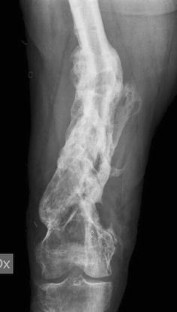

Fig. 1

Fig. 2

Fig. 3

Fig. 4

Fig. 5

Fig. 6